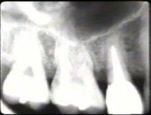

La radiografía periapical muestra al cuadrante superior derecho,

en particular

al premolar, una bolsa infraósea en mesial y distal |